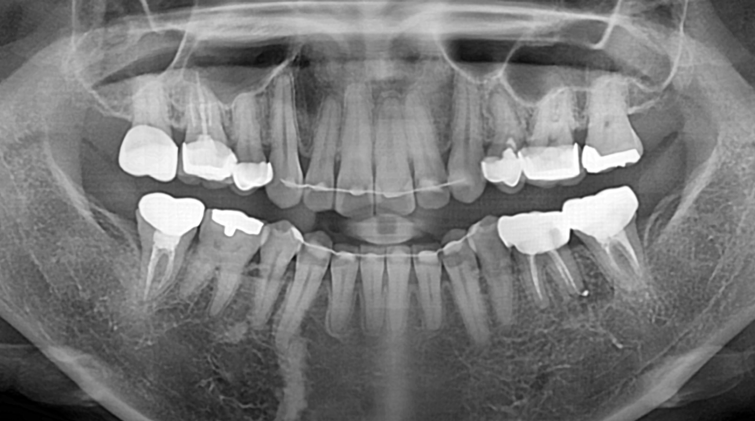

발치 즉시 임플란트.

Before